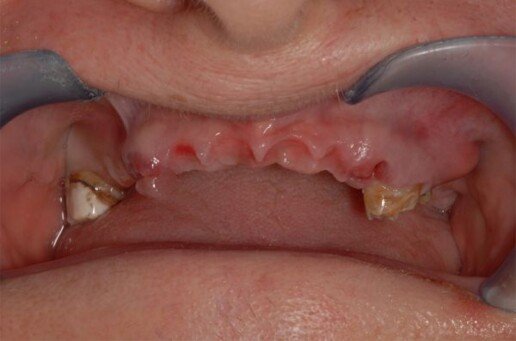

Riabilitazione totale superiore e inferiore su impianti. Gli esiti di una paradontite grave portano alla perdita totale dei denti. E’ necessario ricostruire sia i denti sia i tessuti molli e anche l’osso per il sostegno delle labbra.

Prima

Dopo